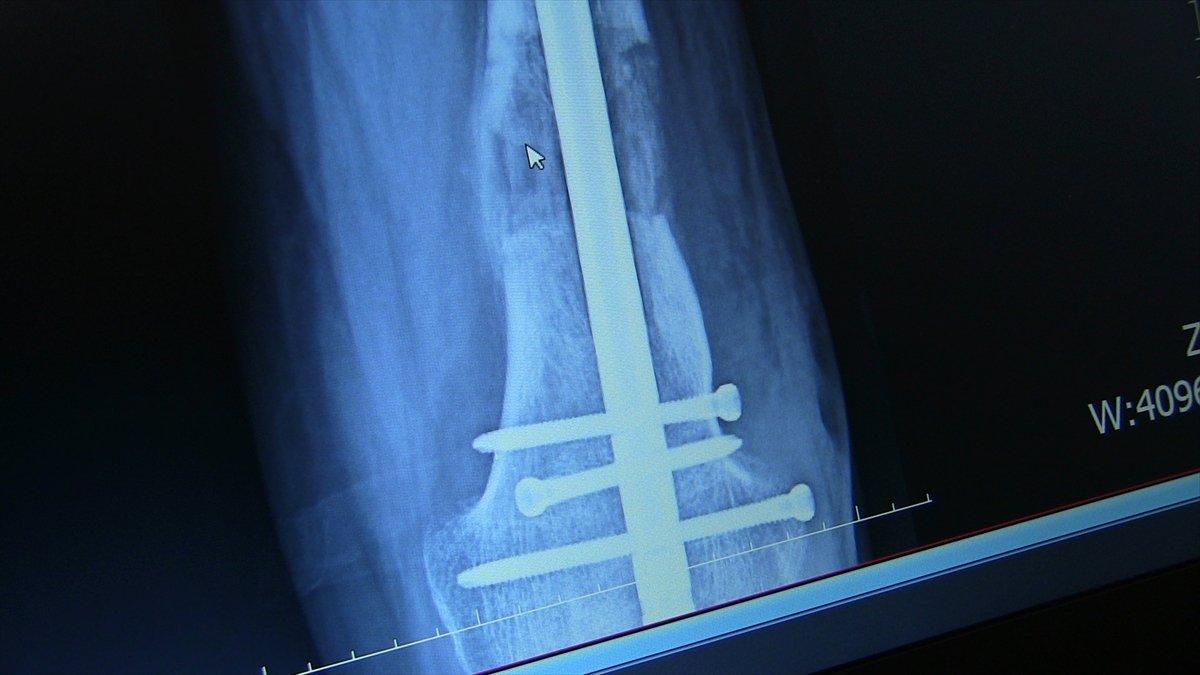

PLATİN VE ÇİVİLERLE AYAĞINDAKİ KISALIK GİDERİLDİ

Operasyonu gerçekleştiren Farabi Hastanesi Ortopedi ve Travmatoloji Uzmanı Prof. Dr. Mehmet Arazi ise hastanın kendilerine müracaat ettiğinde, sol bacağında ciddi bir kısalık, diz bölgesinde eğrilik ve ayağında fiziksel bozukluk olduğunu söyledi.

Hastanın yaşı ilerledikçe yürüme probleminin arttığını, sol ayağının sadece ayak parmaklarını yere basabildiğini dile getiren Arazi, "Hastamızın, ardışık ameliyatlarla bacağındaki kemikleri uzatabilme, dizindeki ve ayağındaki problemleri giderme kararı aldık. Yaptığımız ameliyatla ilk olarak bacağındaki şekil bozukluğunu düzelttik. Ardından tıbbi olarak kullandığımız çivi ve platinlerle dizin üstündeki ve dizin altındaki kemiği uzattık. Ardından topuk ve ayak bileğindeki bozukluk için de bir operasyon yaptık. Şu anda sağlığı iyi durumda." diye konuştu.